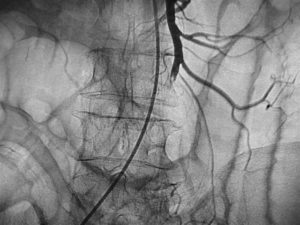

Специфическим методом диагностики острой окклюзии мезентериальных сосудов является селективная мезентерикография, которая уже на ранней стадии заболевания может выявить отсутствие кровотока в стволе и ветвях брыжеечной артерии.

- ангиография (контрастный метод исследования) позволяет обнаружить тромбоз и определить его локализацию;

На ранней стадии развития болезни, когда изменения обратимы, диагностировать тромбоз позволят только ангиография и лапароскопия. Другие методы будут информативны только в случае тяжелой формы патологии.

- селективная ангиография позволяет сделать наиболее точное заключение (тромбоз брыжеечных сосудов диагностируют, если на ангиограммах не определяется основной артериальный ствол).